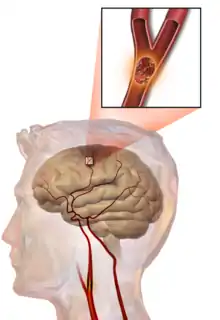

Illustration of an embolic stroke, showing a blockage lodged in a blood vessel.

In thrombotic stroke, a thrombus[39] (blood clot) usually forms around atherosclerotic plaques. Since blockage of the artery is gradual, onset of symptomatic thrombotic strokes is slower than that of a hemorrhagic stroke. A thrombus itself (even if it does not completely block the blood vessel) can lead to an embolic stroke (see below) if the thrombus breaks off and travels in the bloodstream, at which point it is called an embolus. Two types of thrombosis can cause stroke: